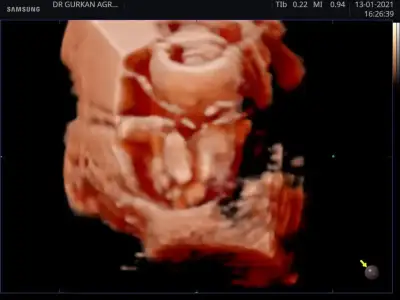

Hayirli sağlıklı olsun.dr mu soyledi.usg paylasmistin degil mi burada.gelecegi parlak cok sansli olsun bebegin.Benim ki. Kız kesin

Evet Dr söyledi teşekkürlerHayirli sağlıklı olsun.dr mu soyledi.usg paylasmistin degil mi burada.gelecegi parlak cok sansli olsun bebegin.

Ben de kız demistim .o haftalik ultrason kaginda daha belli oluyor cinciyet tahmini.çıkınti paralel oldugu icin kız demistim ben de.buradaki fotoda net belli sizin.seni çok iyi anlıyorum.benim de iki kızım var.ve ücuncuyu istiyoruz.olmadi 5 aydir gebelik.hayırlısı olsun.saglikli olsun en önemlisi.Rabbimin vardır bildiği .verdiyse en hayırlısını vermistir.gönlünü ferah tut .Evet Dr söyledi teşekkürlerEki Görüntüle 2764435

Ama çoğu kişi erkek bu bebek diyorBen de kız demistim .o haftalik ultrason kaginda daha belli oluyor cinciyet tahmini.çıkınti paralel oldugu icin kız demistim ben de.buradaki fotoda net belli sizin.seni çok iyi anlıyorum.benim de iki kızım var.ve ücuncuyu istiyoruz.olmadi 5 aydir gebelik.hayırlısı olsun.saglikli olsun en önemlisi.Rabbimin vardır bildiği .verdiyse en hayırlısını vermistir.gönlünü ferah tut .

Ben cizmedim isegramdan bu sayfa çizdi cinsiyetini öğren diye bi sayfaSen ustunu cizmissin bilemedim simdi.baska bir dr a da gitsen imkanın vaktin varsa için rahat olur .

Evet o sayfa bana erkek dedi bugün öğrenmeye gideceğim bende hayırlısı olsunBen cizmedim isegramdan bu sayfa çizdi cinsiyetini öğren diye bi sayfa